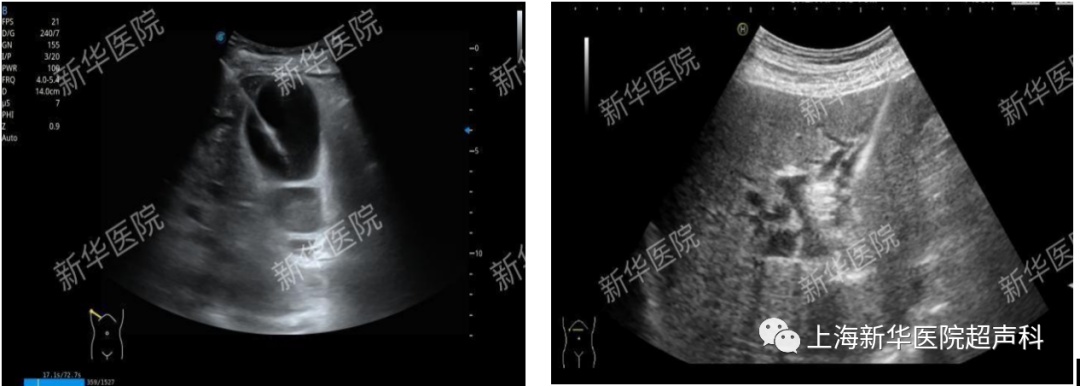

(2)胆囊造瘘、肾造瘘、膀胱造瘘、经皮肝胆管穿刺置管引流术(PTCD)。

胆囊造瘘术 经皮肝胆管穿刺置管引流术(PTCD)